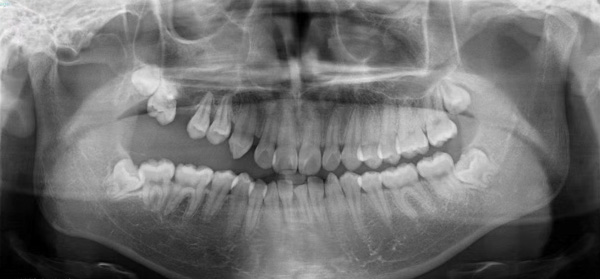

患者小潘(化名)是一名花季少年,5年前发现右侧牙齿无法咬合,随着年龄的增长,症状越来越严重,遂来到柳州市人民医院口腔科就诊,经仔细检查,确诊为右侧先天性颌骨畸形伴有上颌牙列缺损。

“上颌骨作为面中部1/3的骨性支撑,不仅决定了面中部的突度,还对患者的露齿、上牙中线的偏斜、牙合平面的偏斜等产生影响。”据口腔科副主任医师刘彦杰介绍,该患者右侧面部较左侧面部较小,右口角向上歪斜,右上唇较左侧薄,口内咬合紊乱,右侧开牙合,右上颌高出颌平面3-5cm,右下颌舌倾。如果不加以干预,可能会造成咬合紊乱加剧,面部愈发不对称,甚至累及颞下颌关节导致颞下颌关节紊乱,最终影响面部颌口腔功能,进食说话都受到影响。

手术当天,口腔科手术团队首先按照术前设计并3D模拟的截骨导板对右侧上颌骨进行精准分离,按照术前设计的咬合导板精确移动上颌骨达到预定位点,最后精准的使用坚强内固定固位。经过4个小时的努力,完成了正颌手术,待拆除钛板后即可进行咬合关系和对称面型治疗。